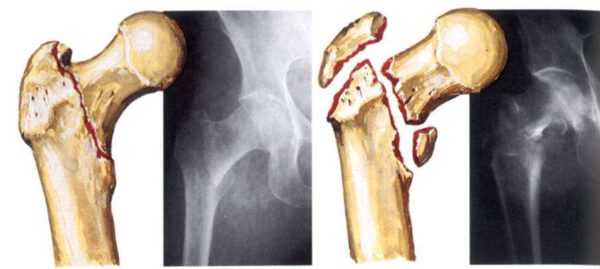

Перелом шейки бедра – одна из наиболее частых травм опорно-двигательного аппарата у лиц пожилого возраста, обусловленная снижением плотности костной ткани. Вколоченный перелом бедра может возникнуть даже при незначительном воздействии. При подобной травме отломки бедренной кости вколачиваются друг в друга, и функции конечности могут оставаться ненарушенными, что затрудняет постановку диагноза.

С возрастом, особенно у женщин в период менопаузы, в результате гормональных изменений снижается плотность костной ткани, и риск патологического перелома резко возрастает. Перелом шейки бедра может возникнуть не только при падении или сильном ударе, но и просто при неосторожном движении, ушибе или даже спонтанно. При вколоченном переломе отломки кости вклиниваются или надвигаются друг на друга, увеличивается угол между шейкой и диафизом бедренной кости. По этой причине функция конечности может оставаться ненарушенной, и пострадавший не догадывается о серьезности травмы.

Точный диагноз устанавливается после тщательного осмотра, сбора анамнеза и рентгенографического исследования пострадавшей области. Чтобы получить полное представление о картине повреждений, рентгенографический снимок делают в 2 или 3 проекциях.

- Типу смещения – вколоченные (отломки находятся внутри друг друга), вальгусные (головка смещается внутрь и вниз).

- Анатомическому положению – трансцервикальные (проходящие через шейку), субкапитальные (возле головки), базисцервикальные (у основания шейки).

Вколоченный перелом

Перелом наблюдается внутри сустава, поэтому двигательная функция ноги нарушается не всегда. В процессе получения травмы один из костных осколков проникает в другой, вследствие чего у пациентов возникают умеренные хронические боли.

Вколоченный перелом шейки бедра сопровождается деформацией и смещением головки многоосного сустава и укорачиванием конечности. Патология протекает практически бессимптомно, поэтому пациенты часто обращаются за помощью к ортопеду уже при появлении некротических изменений в тканях.